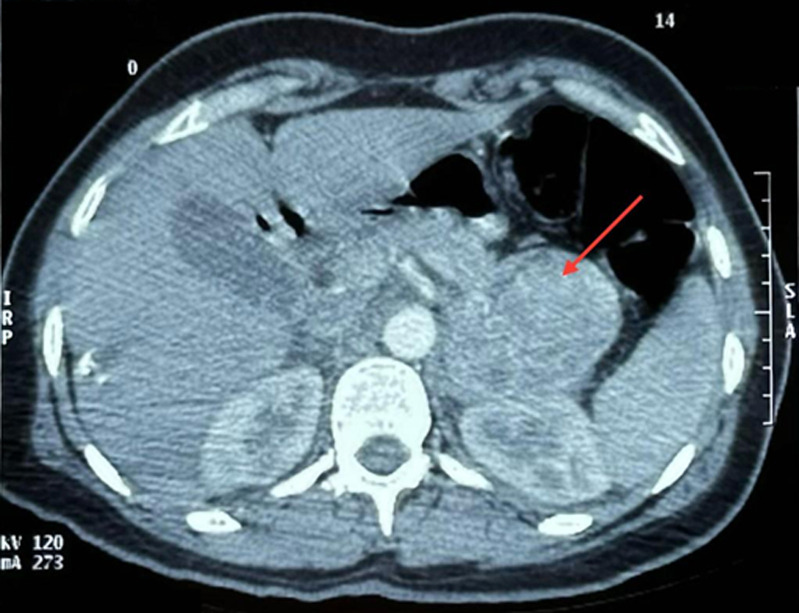

Takotsubo心肌病通常由继发于各种应激因素的严重肾上腺素能激增引发。在罕见的情况下,过量的儿茶酚胺分泌由于嗜铬细胞瘤可能是原因。典型表现为左心室尖部运动障碍。在这个病例报告中,我们描述了一个不典型的takotsubo心肌病病例,其特征是左心室下壁顶端和中间段运动不足,导致发现潜在的嗜铬细胞瘤。虽然这种关联是罕见的,但考虑它是至关重要的,特别是在非典型的形式,因为一旦肿瘤被切除,这种现象是可逆的。

Takotsubo cardiomyopathy is typically triggered by severe adrenergic surges secondary to various stress factors. In rare cases, excessive catecholamine secretion due to a pheochromocytoma may be the cause. It is typically manifested by dyskinesia of the apex of the left ventricle. In this case report, we describe an atypical case of takotsubo cardiomyopathy, characterized by hypokinesia of the apical and mid-segments of the inferior wall of the left ventricle, which led to the discovery of an underlying pheochromocytoma. Although this association is rare, it is crucial to consider it, especially in atypical forms, as once the tumor is resected, the phenomenon becomes reversible.